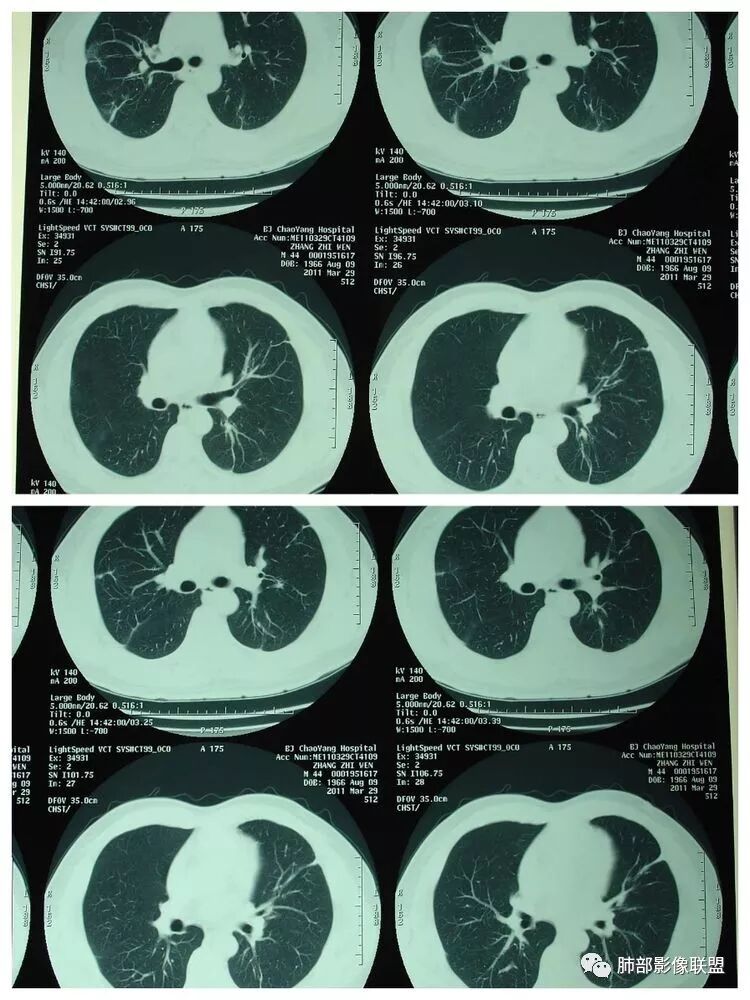

下面是一例几乎一样的肺克:

肺克的影像表现(唐绍宏总结):分布:单侧上叶病变,以右肺上叶多见;患者长期卧床则双脚下肺后基底段分布(国外下肺多见,可能与平均寿命长,卧床及住托老机构多有关) ;如多叶段病变,则以肺上叶后段或下叶后基底段为最明显形态:气管壁增厚、磨玻璃、小叶实变、节段实变、大叶实变,坏死小空洞(直径小于2cm) ,少量胸腔积液50%、脓胸20%特点:早期气管壁增厚较明显、广泛,越靠近病灶越明显,越靠近肺门越明显,见于实变病灶外,偶尔见于磨玻璃影内(支气管通气征) ;未经抗生素治疗,实变病灶内无支气管通气征;早期即可出现坏死,无论坏死还是空洞,绝大多数直径小于2cm (可能与此菌有厚夹膜有关,参考隐球菌)